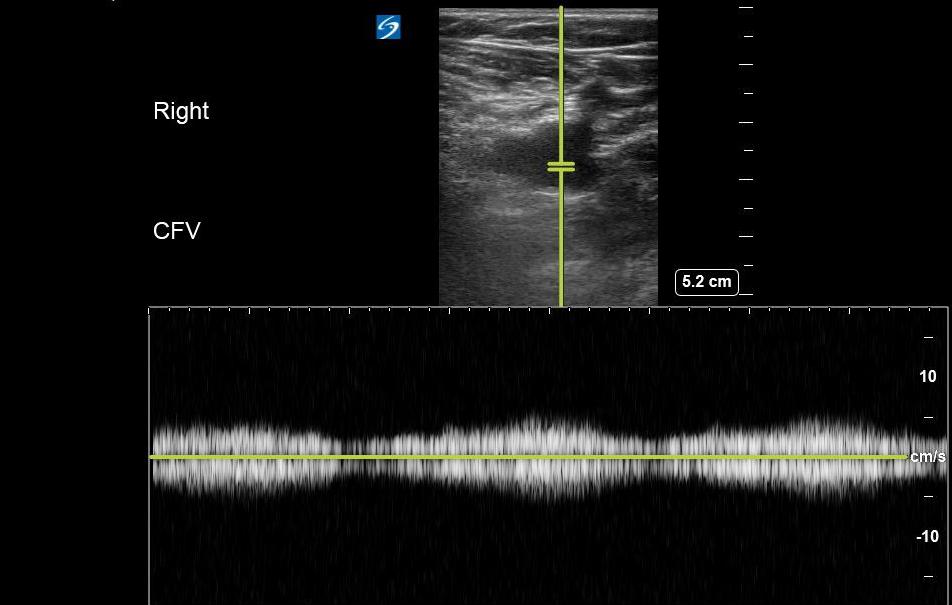

- Respiratory variation/phasic flow

- Involves placing the transducer on the leg, typically at the CFV, and setting the ultrasound machine to spectral (pulsed wave) Doppler mode.

- Flow velocity in deep venous structures varies with the respiratory cycle and changes in intrathoracic pressure.

- A lack of variation in flow may be suggestive of an obstructive process (eg, thrombus, compressive pathology) along the venous system between the proximal inferior vena cava and point of transducer placement. (Figure 17)

- Figure 17. Respiratory variation seen at the CFV with Pulsed wave Doppler.